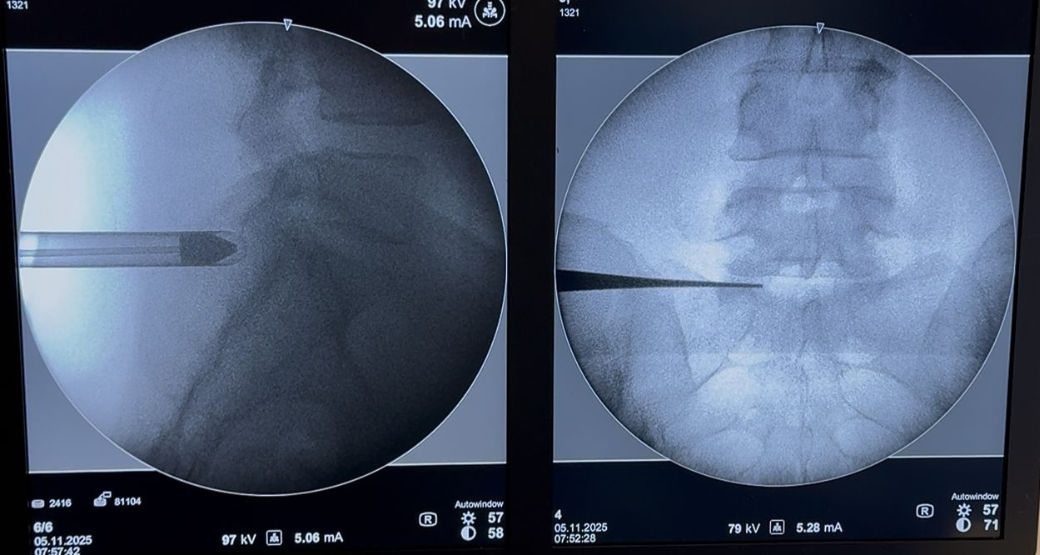

Cirurgia endoscópica para extrusão de hérnia discal em 05.11.2025 às 6h

Técnica Cirúrgica

O acesso interlaminar com ótica de estenose a opção preferida pelos cirurgiões. Ela permite a utilização de instrumentos maiores e eventual drilagem óssea - processo de perfurar e desgastar o osso -, para ampliar o campo operatório e reduzir o tempo de exposição da raiz.

“Procedemos à drilagem lateral da lâmina, em direção ao pedículo esquerdo. Após a remoção do ligamento amarelo, observamos a raiz espinhal lateralizada, deslocada posteriormente e, lateralmente, por volumosa hérnia extrusa intracanalar, ou seja, ruptura do anel fibroso”, acrescentam.